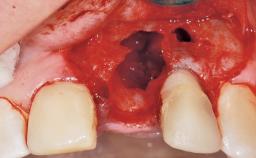

Immediate Placement of an Implant in a Maxillary Left Central Incisor Site

A 33-year-old female patient presented with an upper left central incisor that required extraction after a failed endodontic therapy. The tooth had been traumatized when the patient was a teenager and had undergone several endodontic treatments, including two apicectomy procedures. The patient was in good health and did not smoke. Clinical examination showed that the patient had a high lip line. In full smile, the gingival margins of the upper teeth were visible to the first molars. The gingival margins of central incisors 11 and 21 were only just showing. Examination of tooth 21 confirmed that the tooth was mobile and had hypererupted by 1 mm.

Placement Protocol Immediate implant placement

Tooth Site Maxillary incisor or canine

Socket Morphology Single-root socket

Socket Integrity Damage to one or more bone walls

Bone Volume Damage to one or more socket walls